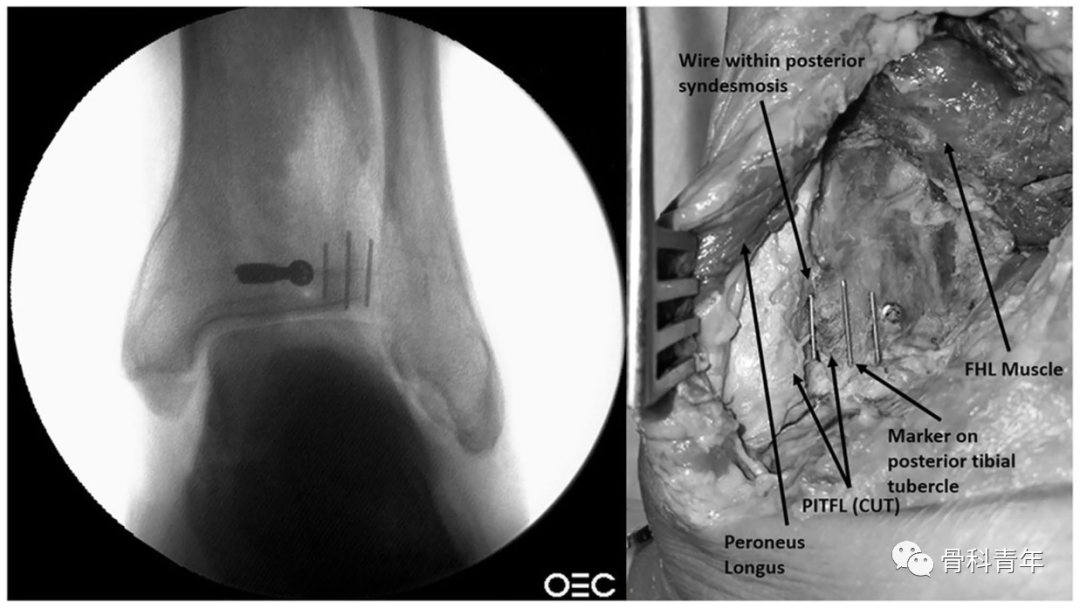

文章首先定义踝穴位上PVSL(Posteromedial vertical syndesmotic line)线,该线为在踝穴位上,下胫腓间隙中胫骨后内侧皮质缘从后向前过渡的投影线。

▲ 图示PVSL线与其在透视下的影像。

为了确定PVSL线是否可代表下胫腓间隙的内侧缘,研究者通过在下胫腓间隙内侧缘放置显影标识,并在该标识的内侧与外侧放置标识,以明确PVSL线是否易于辨别。

该例后踝螺钉穿入下胫腓的标本在CT横断中可明确。

依上述研究结果,在如下的后踝钢板固定中,透视钢板部分位于PVSL线外侧,有影响下胫腓风险,因此将钢板内移至PVSL线内。

▲ 图中白色虚线即为PVSL线。